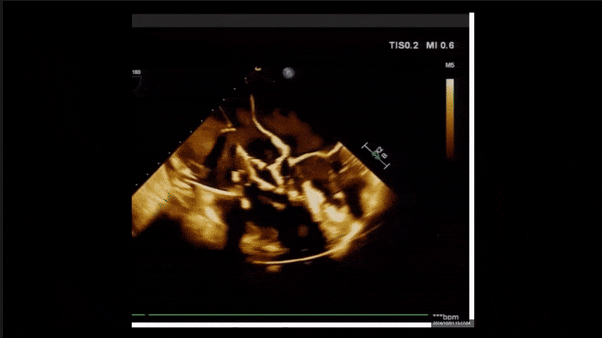

術(shù)后即刻返流

術(shù)后即刻返流三維

術(shù)后三維超聲

術(shù)后即刻經(jīng)食道超聲可見,三尖瓣假體瓣膜位置合適,牛心包瓣葉運動狀態(tài)良好,開閉正常,瓣周及瓣葉對合緣處未見明顯返流,心電圖及心包狀態(tài)較術(shù)前無明顯變化。